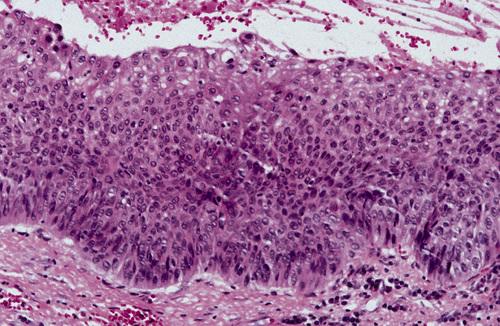

This noninflamed cyst shows a thin, nonkeratinized epithelial lining and a loosely arranged fibrous connective tissue wall.

dentigerous cyst, noninflamed

This inflamed cyst shows a thick epithelial lining with hyperplastic rete ridges and diffuse chronic inflammatory infiltrate.

dentigerous cyst, inflammed